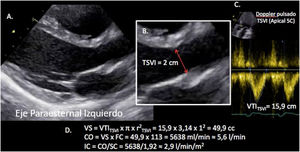

Valoración del volumen sistólico (fig. 2)Se puede realizar por medio de la integral velocidad-tiempo (IVT) y el diámetro del tracto de salida del ventrículo izquierdo (TSVI).

Estimación del volumen sistólico (VS) y del gasto cardiaco (CO) a través de la integral de velocidad (VTI) y radio (r) del tracto de salida del ventrículo izquierdo (TSVI). A) Paraesternal izquierdo ventrículo izquierdo en sístole. B) Zoom TSVI. C) Doppler pulsado TSVI 5C apical. D) Cálculos.

Un IVTTSVI<11cm se correlaciona con un índice cardiaco <2 l/min17,18.